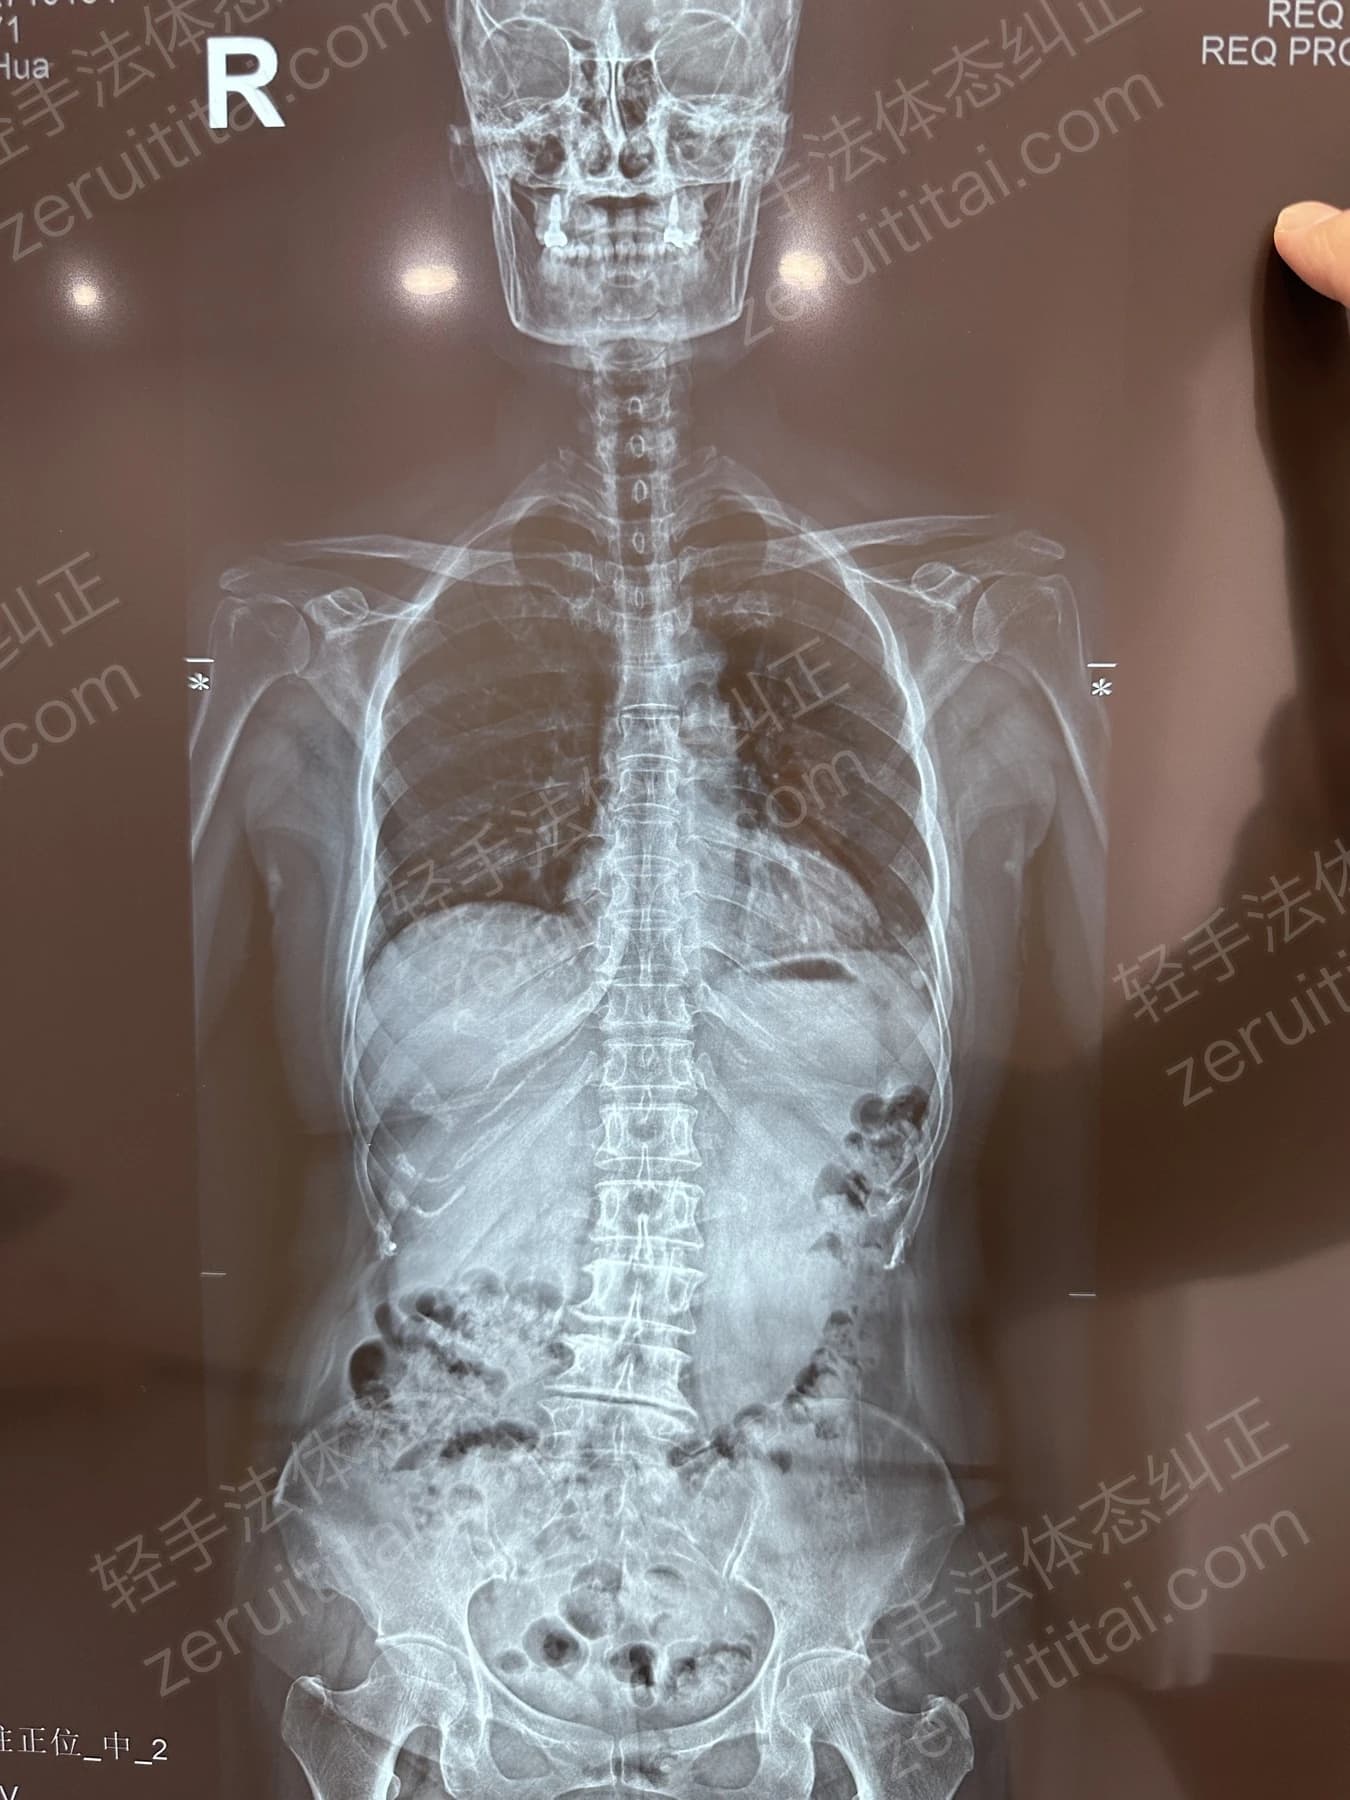

2024.12.18

第 6 次记录

第 6 次记录2024.12.18

正面 X 光